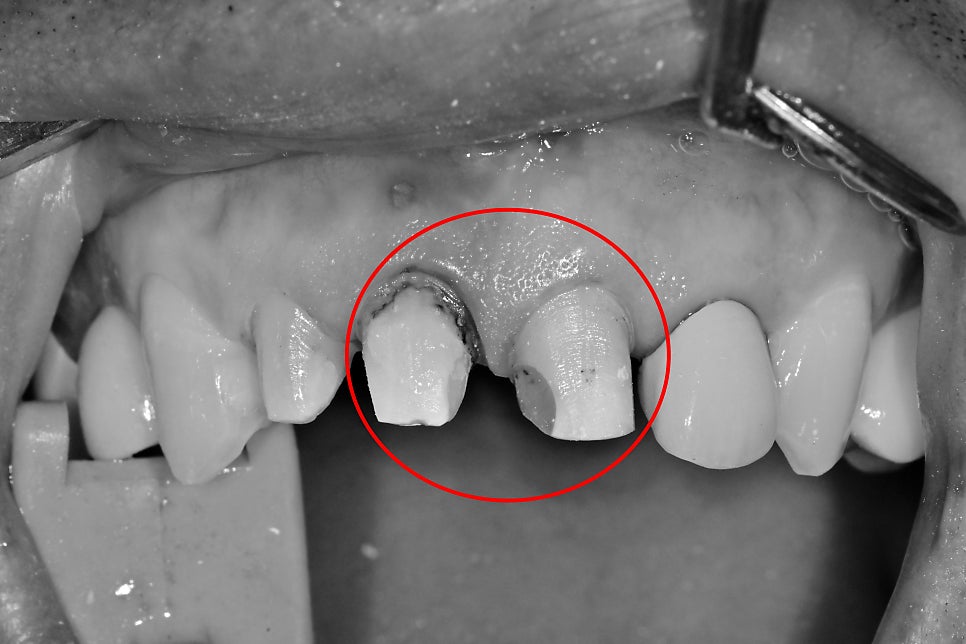

과거 앞니에 한 보철물 주변 잇몸이 불편감으로 내원해 주셨습니다.

치아 보철물은 각기 다른 시기에 제작되었고 1개 혹은 2개 치아가 한 덩어리의 보철물로 이루어져 있습니다.

먼저 화살표를 보시면 잇몸에 동그란 고름 주머니가 생겨있습니다.

과거에 한 보철물의 경계 부위가 시간이 지남에 따라

오염이 되면서 치아 뿌리 쪽에 염증이 생긴 걸로 판단이 됩니다.

앞니 보철 제거 후 재평가

과거에 씌운 보철 경계 부위에 오염으로 인해

통증이 생긴 케이스로 통법대로

신경치료 후 심미보철 단계로 넘어가게 됩니다.